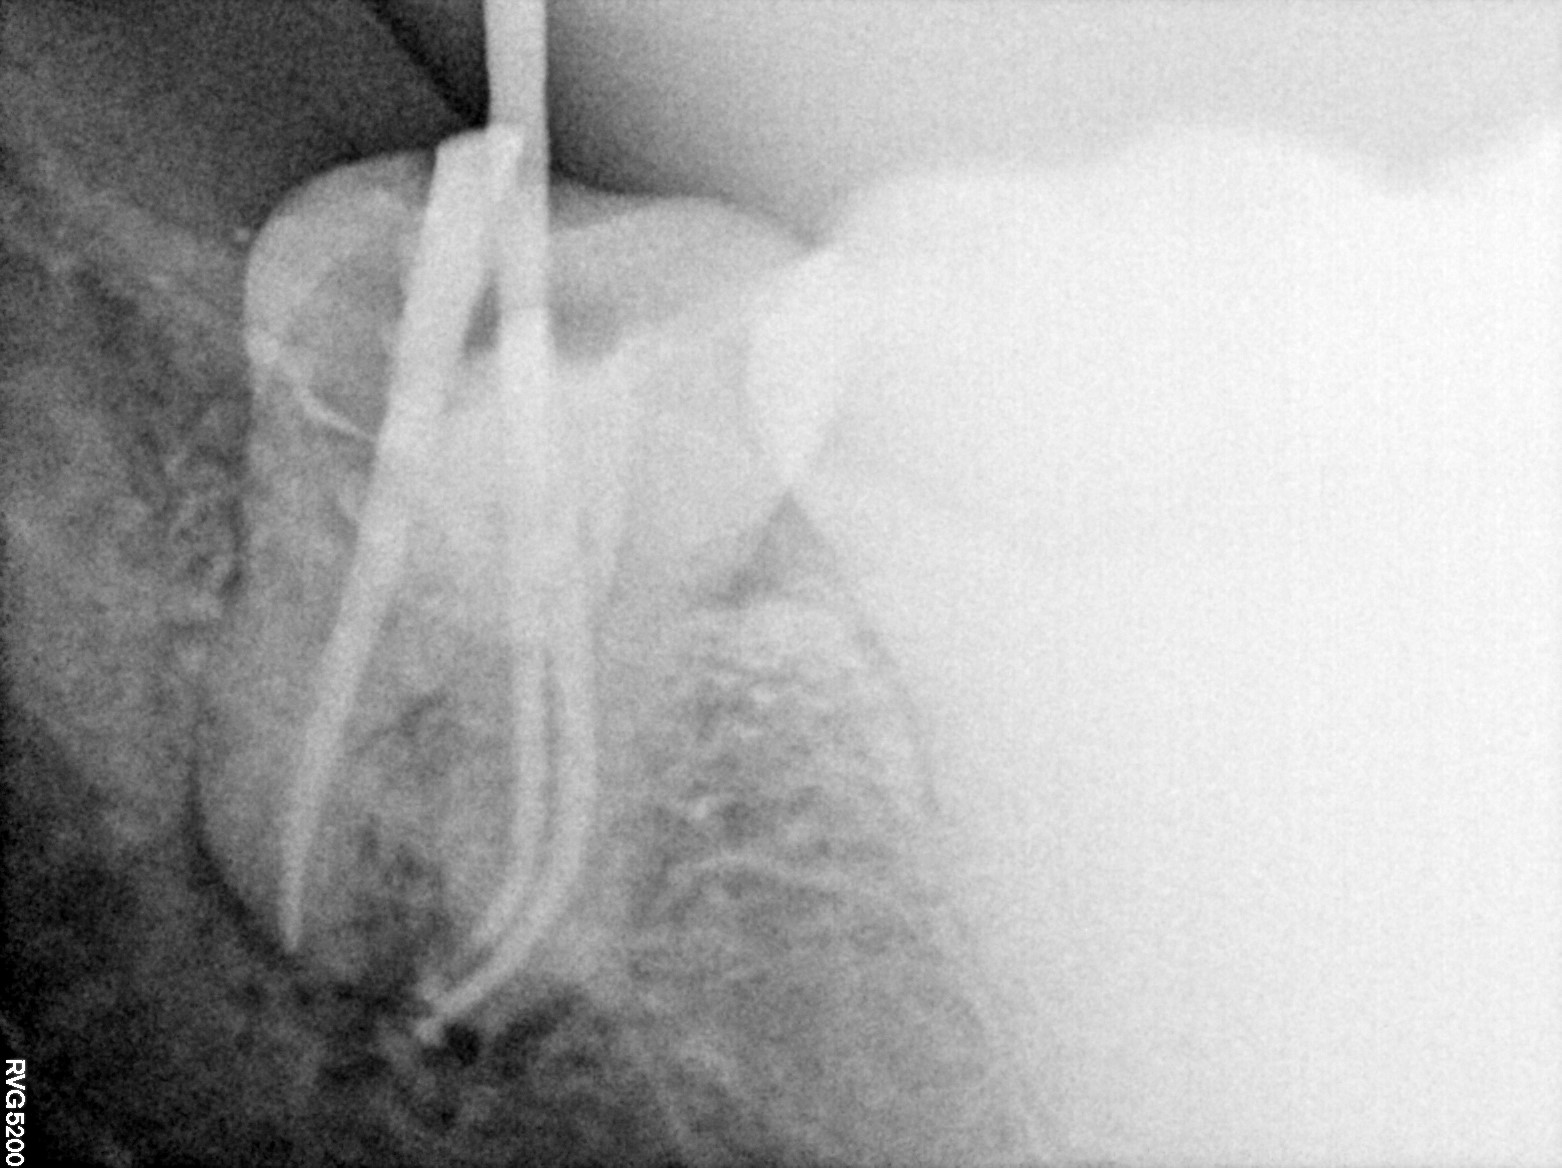

Dental Radiographs FHIR: DocumentReference · LOINC 24641-7

FHIR Bundle

R55.jpg

24641-7

R61.jpg

R65.jpg

R74.jpg

R61 (2).jpg

R63.jpg

R56.jpg

R75.jpg

R64.jpg